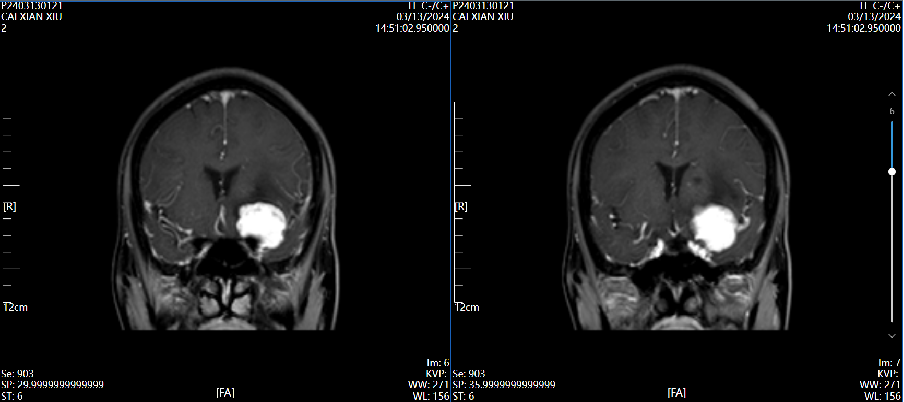

4、辅助检查:头颅磁共振检查提示:左侧前床突占位,约2.8×2.4×2.0cm大小,T1呈等低信号,T2呈等高信号,增强病灶明显强化,宽基底与前颅窝底、前床突相连,看见脑膜尾征。

磁共振增强 2024.03.13